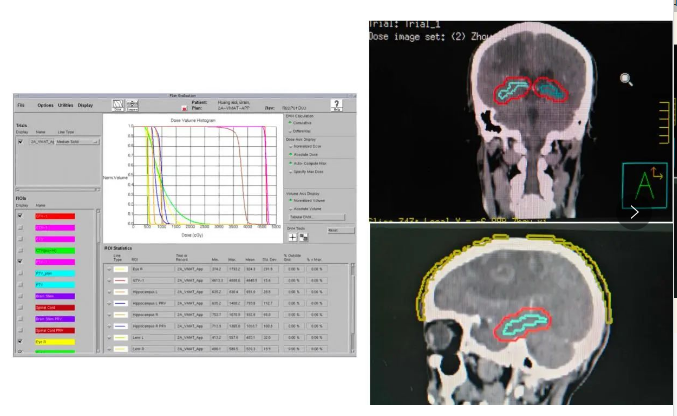

团队年肺癌放疗量在400例以上,常规开展3D-RCT、IMRT、VMAT等调强放疗技术,肺癌立体定向放射治疗(SBRT)在粤西首先开展,海马保护、毛囊保护的肺癌脑转移脑部放射治疗与中国科学院大学附属肿瘤医院合作完成,为国内较早开展。晚期肺癌年治疗4000人次以上,紧跟国内外指南规范地开展肺癌新辅助免疫联合化疗、辅助化疗和靶向治疗、姑息性靶向治疗、免疫治疗、抗血管生成治疗、肺癌脑转移放疗和肺癌全程管理等综合性治疗。参加多项国际、全国多中心肺癌临床研究,为广大患者提供使用新药的机会。

海马保护放疗新技术开展